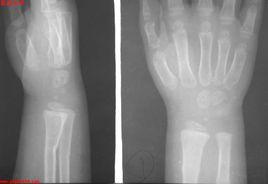

青枝骨折多見於兒童,“青枝”兩個是借用來的,在植物的青嫩枝條中,常常會見到折而不斷的情況。兒童的骨骼中含有較多的有機物,外面包裹的骨外膜由特別的厚,因此在力學上就具有很好的彈性和韌性,不容易折斷,遭受暴力發生骨折就會出現與植物青枝一樣折而不斷的情況,骨科醫生就把這種特殊的骨折稱之為青枝骨折。

由於青枝骨折時,骨骼雖“折”卻仍然未“斷”,因而一般都屬於穩定骨折,通常是不需要手術治療的。四肢骨的青枝骨折用石膏外固定治療都有很好的效果。